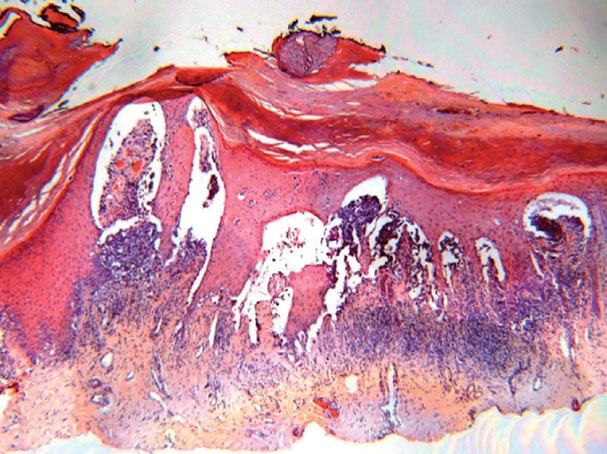

Acral melanoma =ميلانوم النهايات